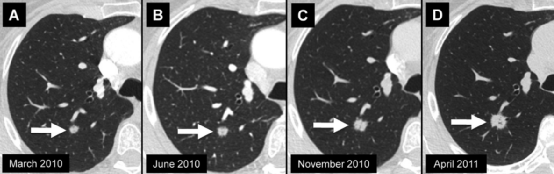

右肺上叶的实性结节 (箭头) 的时间顺序扫描。结节的平均直径为,A、8mm,B、9mm,C、11mm,D、13mm。当我们将最早的图像与最新的图像进行比较时,结节的生长最为明显。手术证实为腺癌。